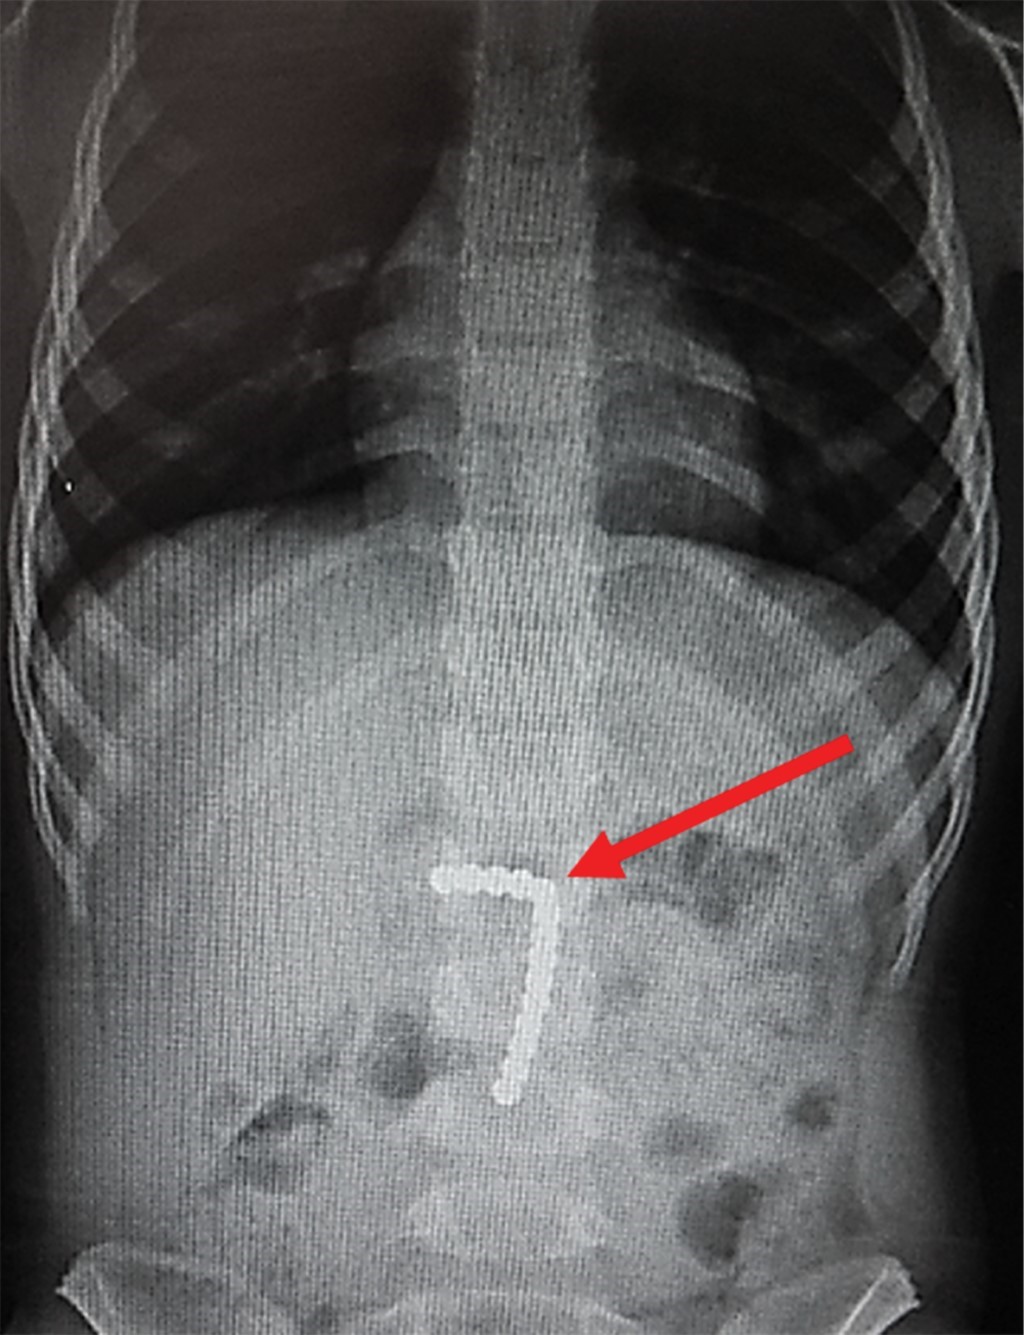

Se trata de paciente femenino de tres años y 11 meses, sin antecedentes de importancia, que refiere ingestión accidental de 17 imanes 28 horas antes del inicio de los síntomas. Presenta disfagia y odinofagia, se toma radiografía simple de tórax que muestra tres imanes localizados en faringe (Figura 1). En la placa de abdomen se observan los 14 imanes restantes (Figura 2). Fue enviada a nuestro hospital para ser evaluada por un servicio de Endoscopía.

Figura 1